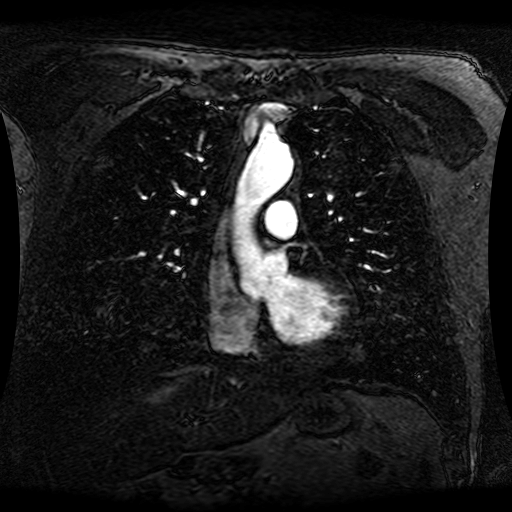

These magnetic resonance angiography (MRA) images show coronal slices acquired from consecutive anteroposterior positions within the torso. The study was performed on a 1.5T General Electric (GE) Signa imaging system with gadolinium-contrast-enhancement for visualization of the cardiopulmonary vasculature. The pulse sequence used was a 3D time-of-flight fast spoiled gradient recalled acquisition in steady state (FSPGR, TR=6.3, TE=1.4, NEX=1, FOV = 40cm, slice thickness = 1.2mm).

This sample image contains 76 frames. It is available in DICOM format (E1154S7I.dcm), as an animated GIF (E1154S7I.gif), as .ogg, .mp4, .webm, and .swf animations (one of which is shown above), or as individual PNG-format frames (see below).